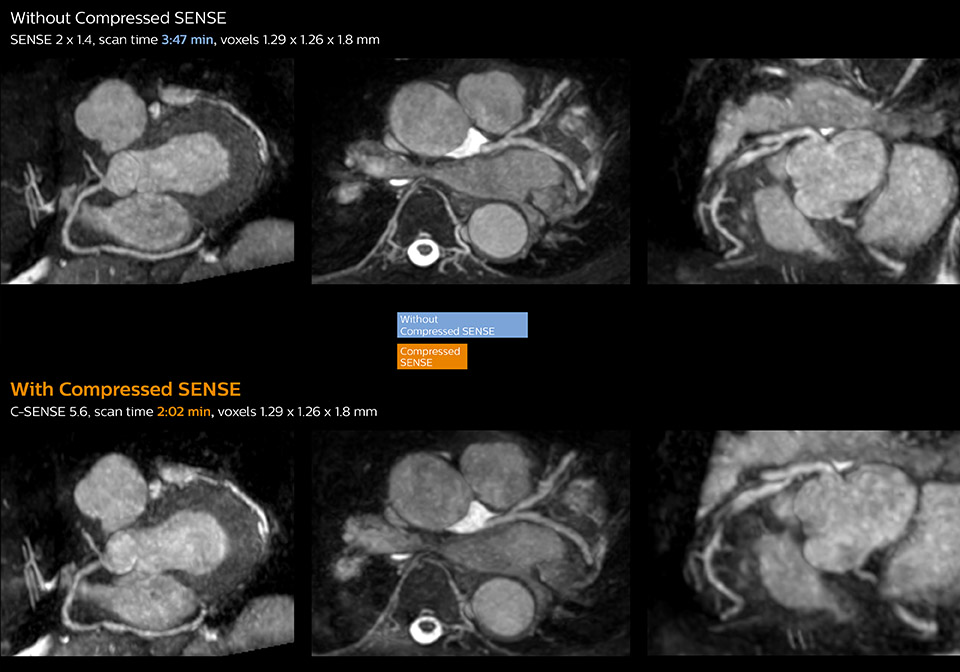

These images of a patient with acute myocardial infarction images were acquired on Ingenia 1.5T with and without Compressed SENSE.

These images with and without Compressed SENSE were acquired on Ingenia 1.5T.

“Typically, in scans with high contrast, such as 2D balanced TFE cine, a quite high C-SENSE factor may be used. When we tried a higher C-SENSE factor, we saw still no significant influence on cardiac ejection fraction, but 2D image quality started to decline. For coronary imaging, we use a C-SENSE factor of 3 in 3D balanced TFE, or even up to 4 when contrast is high.”

“Compressed SENSE has now been implemented in all cardiac exams. Thanks to the acceleration, fewer breath holds are now needed, or breath hold times are shortened. This reduces the burden of the exam for cardiac patients, without affecting the quality of information required for cardiac function analyses,” he says. “Because it’s easier for patients to comply with the breath hold times” “In our previous cardiac cine sequence, we were acquiring two slices during one breath hold. With Compressed SENSE, we increased this to four slices per breath hold. It is also possible to shorten scanning time using a C-SENSE factor 6 without sacrificing image quality.”